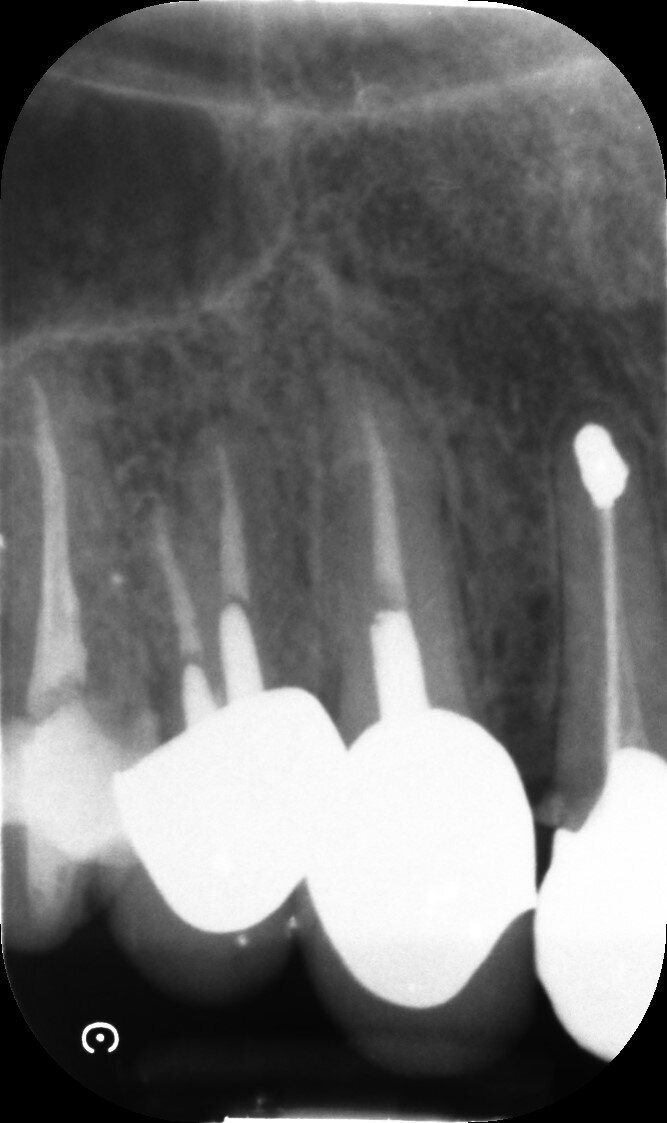

Il dente all’osservazione clinica e radiografica appare devitalizzato e ricostruito per mezzo di una perno moncone fuso e una corona in metallo ceramica collegata ad una corona sul dente 1.4 (Figg. 1, 2). All’esame parodontale si rileva un sondaggio puntiforme in zona palatale che indica la presenza di una frattura radicolare (Fig. 3). La paziente riporta una precedente apicectomia a carico del dente 1.2, come si evince dall’esame come-beam che ne evidenzia gli esiti a carico dell’osso apicale all’elemento 13 (Fig. 4).